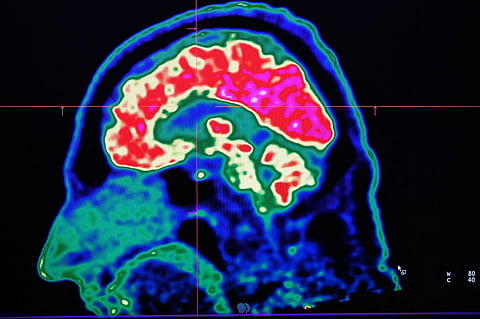

Alzheimer’s is a neurodegenerative disease that gradually damages memory and thinking skills. By the time symptoms such as memory loss appear, brain changes have often been underway for years.

Abnormal tau proteins can form tangled fibres in the brain, disrupting communication between nerve cells. Brain imaging tests can detect these tangles, and earlier research has suggested they may help predict symptom onset.